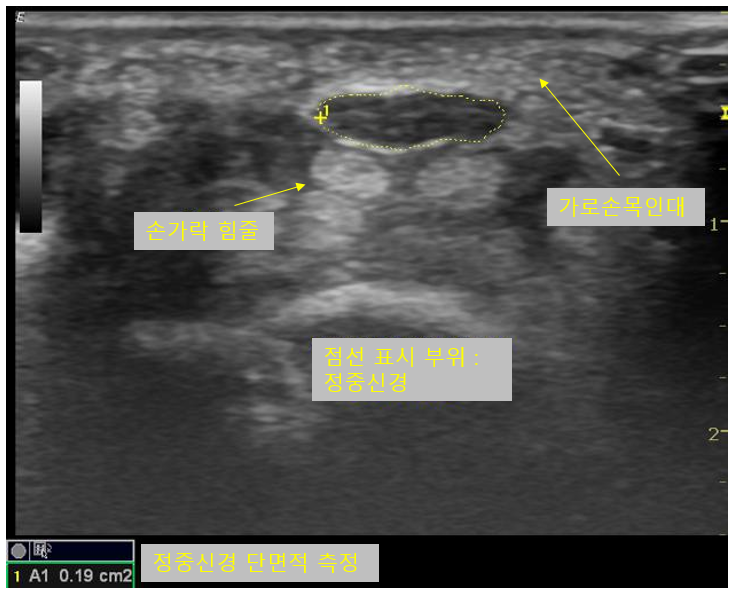

초음파 검사에서 정중신경이 눌려있을 경우 초음파음영이 감소하여 정상보다 어둡게 보이며, 흔히 신경이 벌집모양으로 보인다고 설명하는데 벌집모양이 뚜렷하게 보이지 않고 소실될 수 있습니다. 좀더 객관적으로 데이터화 하기 위해 정중신경의 단면적을 측정할 수 있습니다. 신경이 눌릴 경우엔 눌린 부위보다 근위부에선 신경의 단면적이 증가하게 됩니다. 고무풍선과 같이 탄력성 있는 물체의 한쪽 부분을 눌렀을때를 생각해보시면 이해가 쉬우실것 같습니다.

한 부위에서만 단면적을 측정할 경우 정확성이 떨어질 수 있기 때문에 손목터널 보다 조금더 근위부에서도 측정하여 단면적의 차이가 기준치를 초과하는지 검사하기도 하고, 손목터널에서의 단면적과 전완부에서의 단면적의 비율로 판단하기도 합니다.